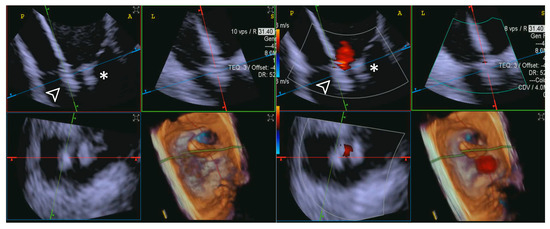

- Step number 5: clocking.

- Step number 6: grasping.

- Step number 7: leaflet insertion.

- Step number 8: evaluation of residual regurgitant jets.